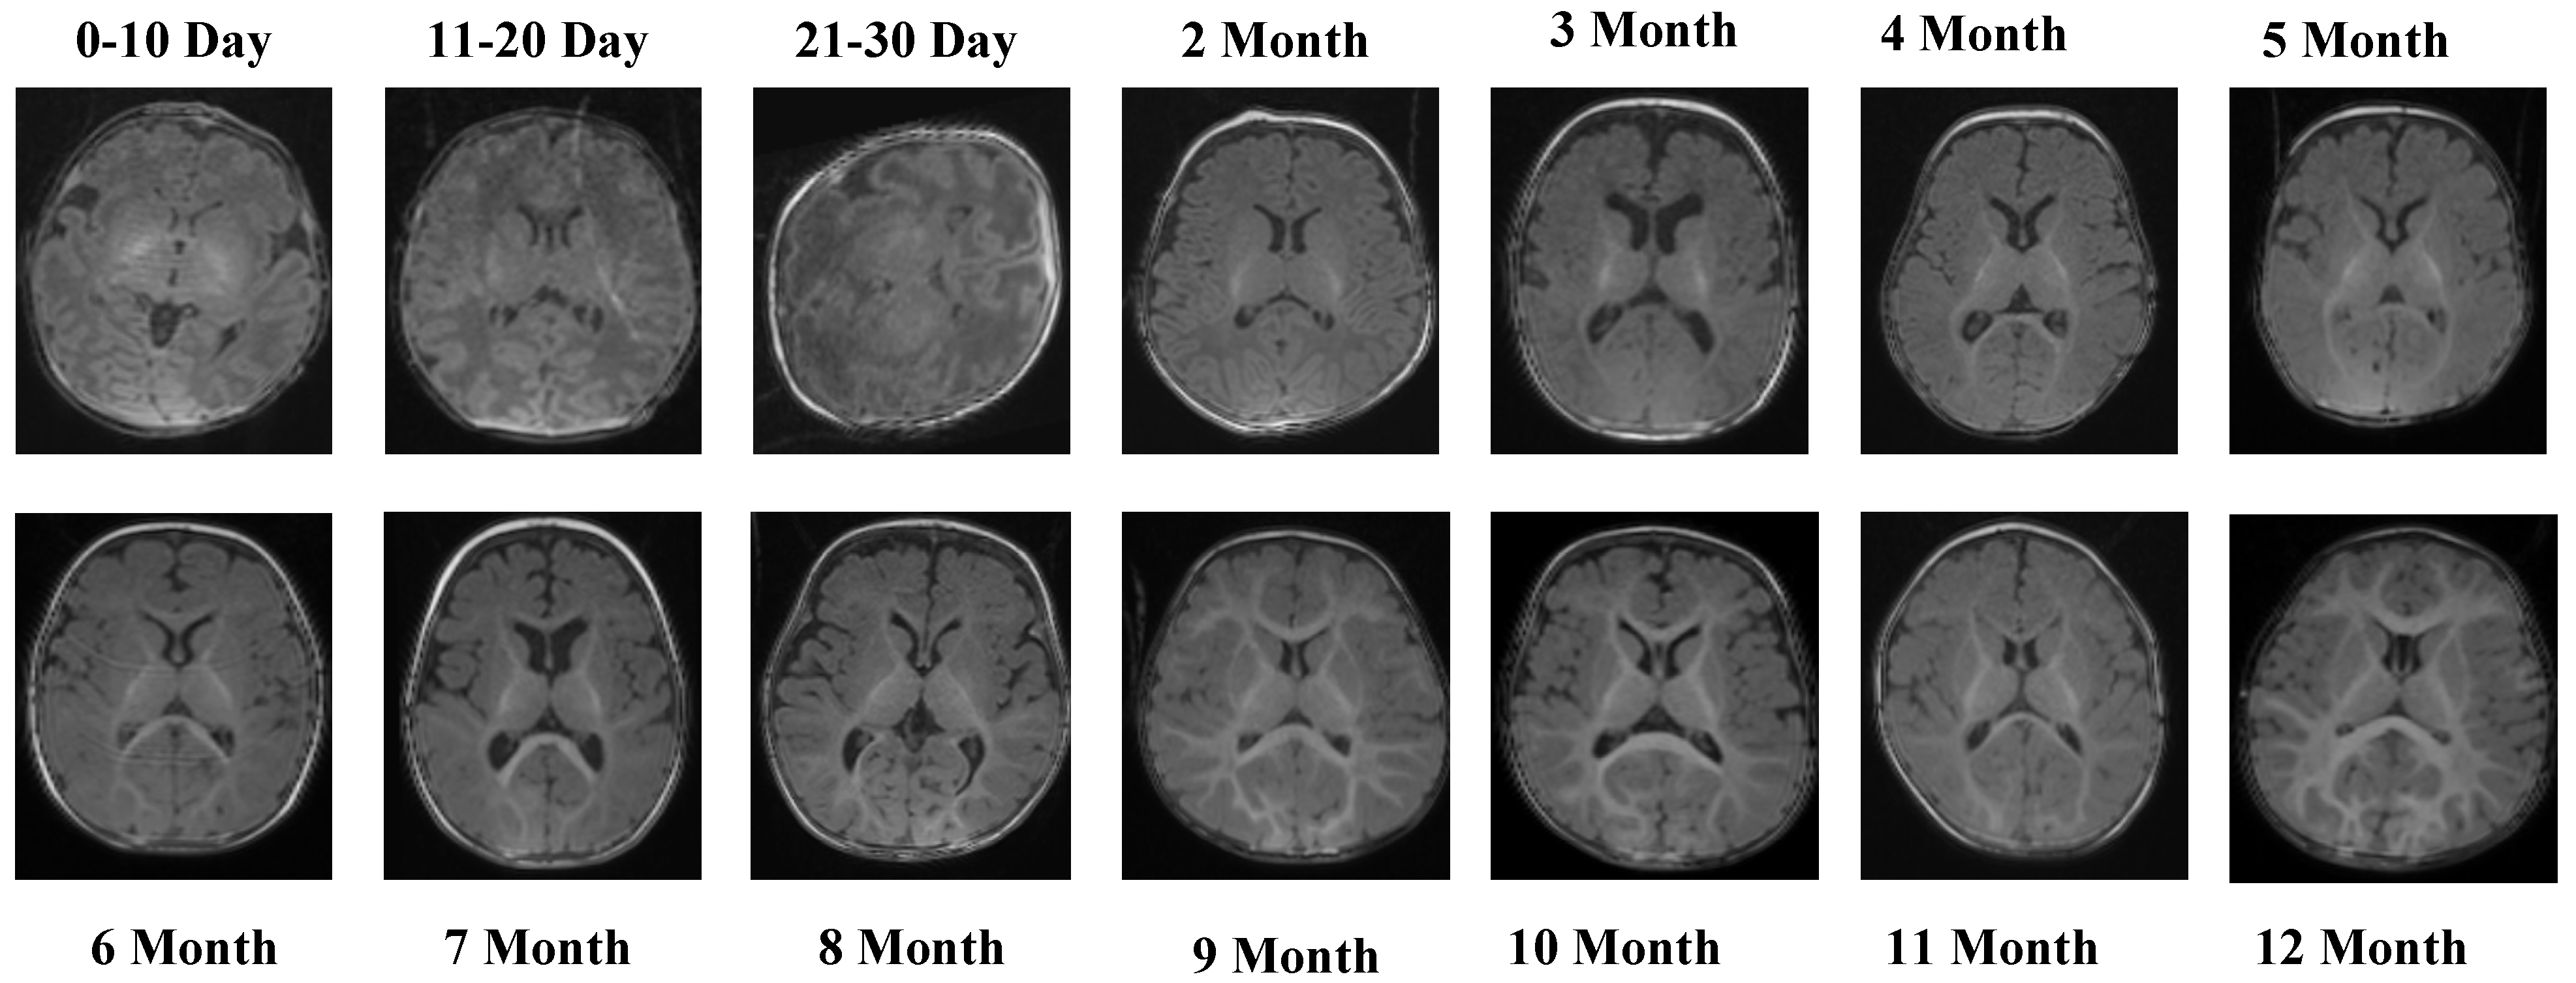

The T1 Male sequence contained 8154 images (6523 for training and 1631 for testing). The data are systematically organized from early neonatal stages (0–10, 11–20, and 21–30 days) to monthly intervals covering 2–12 months. This structured arrangement provides balanced coverage across both early infancy and later developmental stages. Examples of MRI slices from the T1 Female sequence are presented in Figure 2, demonstrating structural variation across neonatal and infant periods.

Figure 2.

MRI slices from the T1 Female sequence.

Figure 2 presents representative MRI slices from the T1 Female sequence, demonstrating structural variability across neonatal and infant stages.

The T1 Female sequence comprised 7754 images, with 6205 used for training and 1549 for testing. Similarly to the male subset, the data follow the same chronological structure, ensuring comparability across sexes. This facilitates a robust evaluation of potential sex-specific developmental differences. Representative samples from the T2 Male sequence are provided in Figure 3, highlighting the contrast-specific features of T2-weighted imaging across developmental stages.